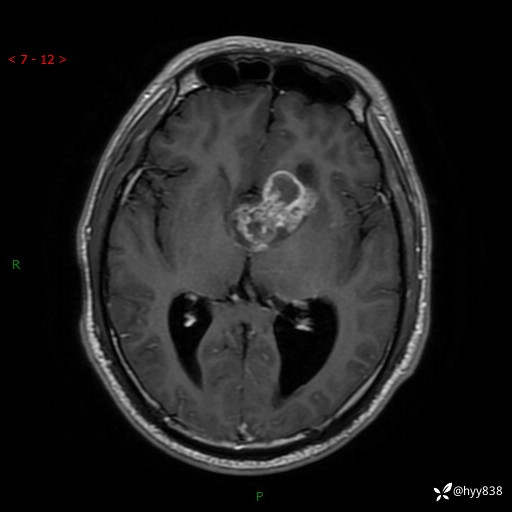

颅脑MRI平扫+增强